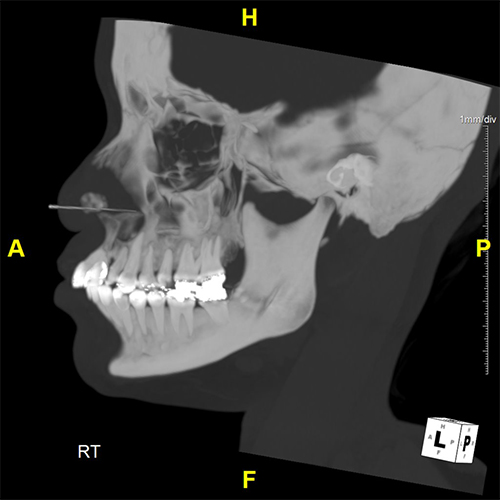

Our Facial Bones Service specializes in the analysis of facial trauma using 3D imaging derived from CT scans. This method involves volume rendering (VR) and segmentation techniques to map the skull base and facial bones, transforming traditional 2D CT images into 3D models. These models provide visualizations of the facial structure, highlighting fractures, dislocations, and other trauma-related anomalies.

This 3D imaging process allows healthcare professionals to assess the extent of facial injuries precisely. It is particularly beneficial for identifying fractures, evaluating the placement of surgical hardware, detecting abscesses, and diagnosing bony metastasis. By providing these precise visual tools, our service supports medical professionals in making informed decisions and optimizing treatment strategies for patients with facial trauma.